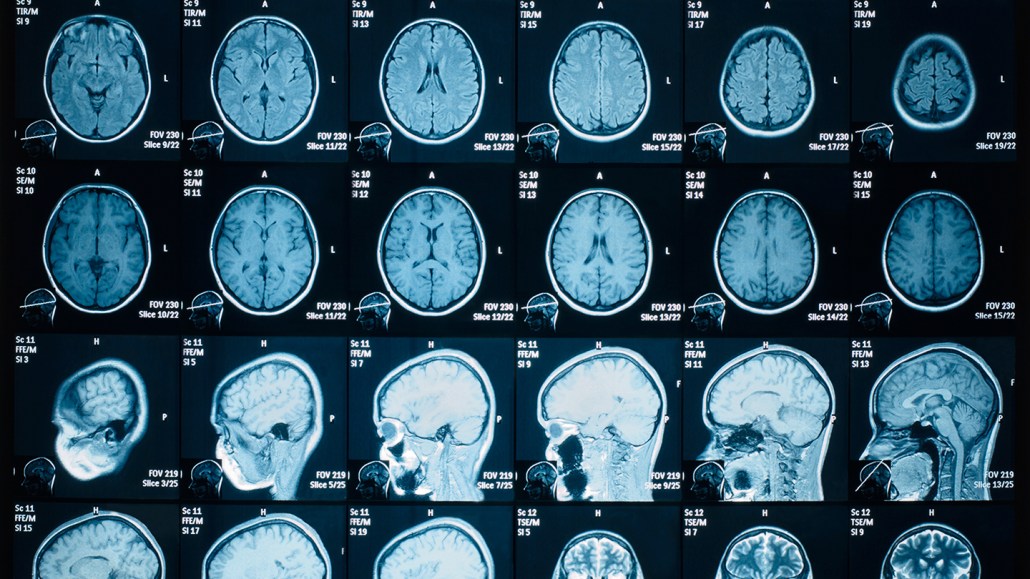

Brain imaging (shown) can reveal when certain regions grow or shrink. A meticulous new brain-scanning study suggests that a bout of COVID-19 can make some parts of the brain smaller. The next big question is what those changes might mean for human health.

The study is one of the first to look at structural changes in the brain before and after a SARS-CoV-2 infection. And the study is meticulous. It was done by an expert group of brain imaging researchers who have been doing this sort of research for a very long time. As part of the UK Biobank project, 785 participants underwent two MRI scans. Between those scans, 401 people had COVID-19 and 384 people did not. By comparing the before and after scans, researchers could spot changes in the people who had COVID-19 and compare those changes with people who didn’t get the infection.